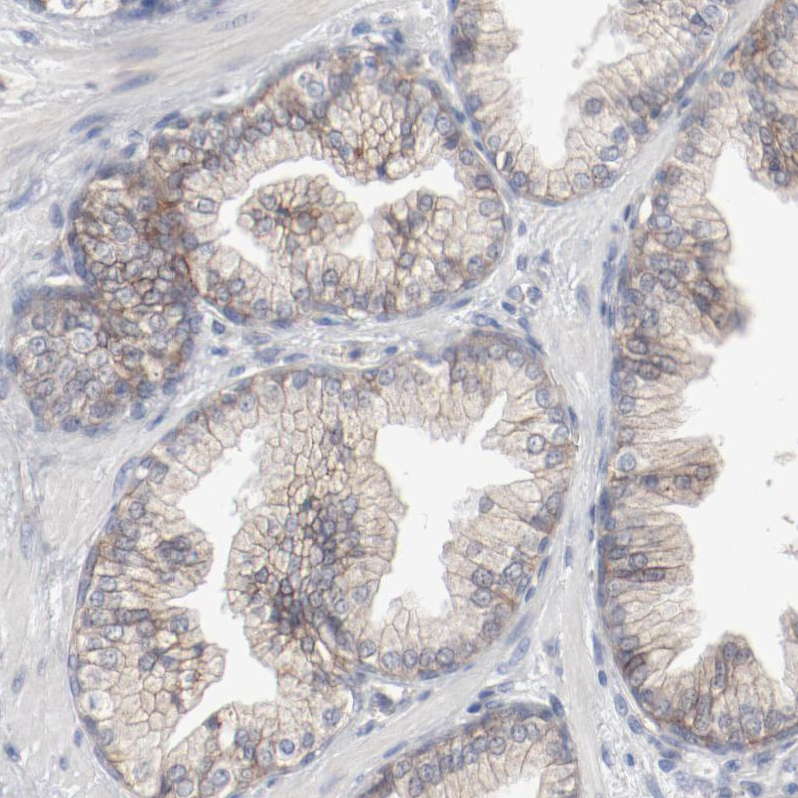

Immunohistochemical staining of human Prostate shows moderate membranous positivity in glandular cells.